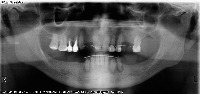

P_Fase_1_v2 Computer Vision Project

Classes (125)

AGS Medikal Implant

AMerOss Implant

Abscess

Amalgam filling

Anthogyr Implant

Bicon Implant

BioHorizons Implant

BioLife Implant

Biomet 3i Implant

Blue Sky Bio Implant

Bone loss

Calculus

Camlog Implant

Caries

Composite filling

Cowellmedi Implant

Crown

Cyst

Filling

Fracture line

Furcation

Impacted

Implant

Nerve

Prefabricated metal post

Prosthesis

Retained root

Root Canal

Root canal filling

Root canal obturation

Root canal treated

Root piece

Sinus

Straumann Implant

The dataset includes 3225 images.

The following pre-processing was applied to each image: